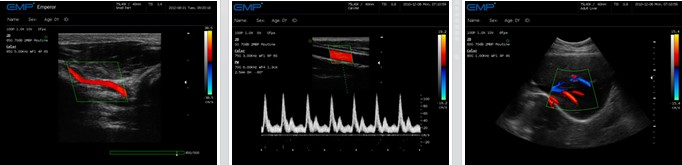

EMP-3000智慧版是恩普历时十余年拥有完全自主研发产权的一款全身应用型彩色多普勒超声诊断系统。这款机型采用全数字化技术,配备了性能稳定的操作系统,外型典雅优美,操作舒适,图像细腻真实,能够满足临床多领域的诊断需求。

● 彩色多普勒(CFM),实时无创显示区域血流信息,检测客观精确

● 频谱多普勒(PW)准确分析定点血流速度,精确提供距离分辨力

● 方向能量图(PDI),显著提高血流成像的灵敏度

临床图片